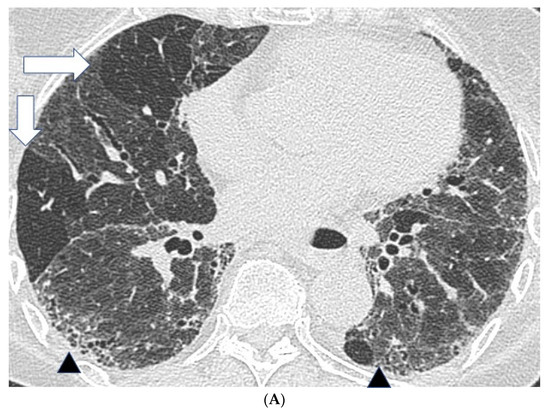

Figure 1. Features suggestive of chronic hypersensitivity pneumonitis in different patients. (A) Spared pulmonary lobules are visible within non-fibrotic lung bilaterally (arrows); background fibrosis is evidenced by peripheral reticulation and traction bronchiectasis (black arrowheads). (B,C) A predilection towards bronchocentricity of the fibrosis in the upper lobes is evident on axial (arrowheads) and coronal (arrows) images. (D) An upper and midzone predominance to the fibrosis, characterised by reticulation and traction bronchiectasis, is seen on a coronal CT. Incidentally, volume loss in the right lung is noticeable by slight tenting and elevation of the right hemidiaphragm (arrow). (E) A UIP pattern with honeycomb cysts is visible in the left midzone of the lung (arrowhead) in a 74-year-old male ex-smoker. A surgical biopsy performed a few years before this CT had demonstrated findings compatible with fibrotic hypersensitivity pneumonitis.

In fibrotic HP, CT patterns including reticulation, traction bronchiectasis and volume loss, with or without evidence of honeycombing, are all seen (Figure 1) [26,28]. Patients often demonstrate an upper lobe predominant distribution of fibrosis, but diffuse and lower lobe predominant changes have also been described. Furthermore, a faint bronchocentricity to the fibrosis can be observed at the lung apices. Similarly, reticulation in fibrotic HP is considered to have a predominantly subpleural or peri-bronchovascular distribution.

Mosaic attenuation with patchy areas of air trapping in a lobular distribution, more obvious on expiratory scans, is another important CT feature in HP. Lobular air trapping represents indirect evidence of small airways obstruction. (Figure 1A) However, mosaic attenuation can also be observed in other fibrotic lung diseases, including fibrotic sarcoidosis and connective tissue disease associated interstitial lung disease, also related to small airways involvement. As a result, lobular air trapping, which is often considered characteristic, may be a relatively non-specific finding. Interlobular septal thickening can be particularly profuse in fibrotic HP, although this is also a feature of fibrotic sarcoidosis. Consolidation is rare in HP and should raise the suspicion of alternative diagnoses such as fibrosing organizing pneumonia or sarcoidosis. Finally, cysts have been reported in 13% of patients with subacute HP but can also be seen in fibrotic HP [29]. The cysts are suspected to be a result of bronchiolar obstruction secondary to peribronchiolar lymphocytic inflammation, similar to that seen in lymphoid interstitial pneumonia.